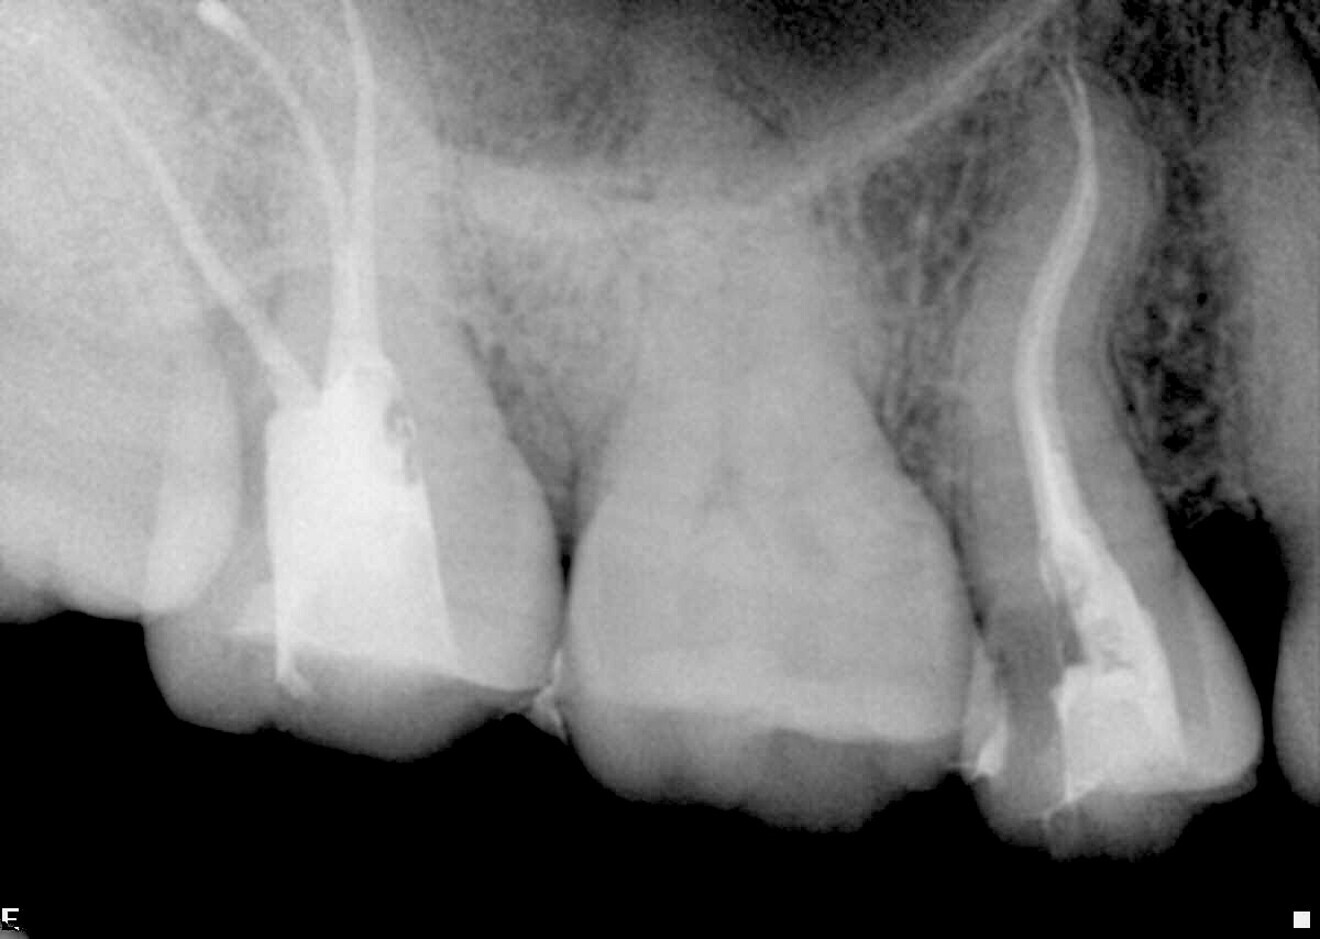

The preoperative radiograph of the premolar offers insight into the complex anatomy and multiple curvatures of the canals (Fig. 4). Two distinct canals are visible, yet they are so closely positioned that they could easily be misinterpreted as one. On the postoperative radiographs, the different apical foramina are clearly identifiable (Figs. 5 & 6). The images also show how well the file respected the original canal anatomy—shaping without excessive coronal enlargement to accommodate the multiple curves. No ledge formation or apical transportation had occurred.

Case 1—Fig. 4: Initial periapical radiograph.

Fig. 5: Post-op periapical radiograph.

ig. 6: Post-op periapical radiograph, angled view.